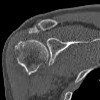

CT of the shoulder joint.

КТ плечевого сустава необходима в сложных клинических ситуациях, требующих детальной визуализации структур исследуемой области. Эта процедура используется для неинформативности более распространенных методов на фоне клинических симптомов поражения плечевого сустава. К последним относятся боль в области сустава во время движений, осевая нагрузка или в состоянии покоя, уменьшение амплитуды движений или их полное отсутствие, увеличение размеров, отечность, деформация, покраснение и повышение температуры кожи выше сустав, образование пальпируемых опухолей, патологические движения и хруст. Исследование назначают при подозрении на рентгеновские и сложные переломы ближнего и внутрисуставного сустава, гемартроз, абсцессы, артрит, артроз, доброкачественные и злокачественные опухоли, врожденные аномалии развития.

Компьютерная томография плечевого сустава может выявить нарушения структурной целостности костей, соответствующих трещинам или переломам, а также смещение поверхностей суставов относительно друг друга, что является неполным или полным сигналом дислокации. Согласно одному исследованию, остеопороз, деформация, сужение суставного пространства, анкилоз - симптомы артрита и остеоартроза, а также скопление крови или гноя в суставной полости - проявления гемартроза, абсцесса. При увеличении контраста можно обнаружить наличие неоваскуляризации при новообразованиях, что определяет степень злокачественности опухоли. На контрастных изображениях видна деформация сосуда или его «перелом» - проявления тромбоза, эмболии, атеросклероза.